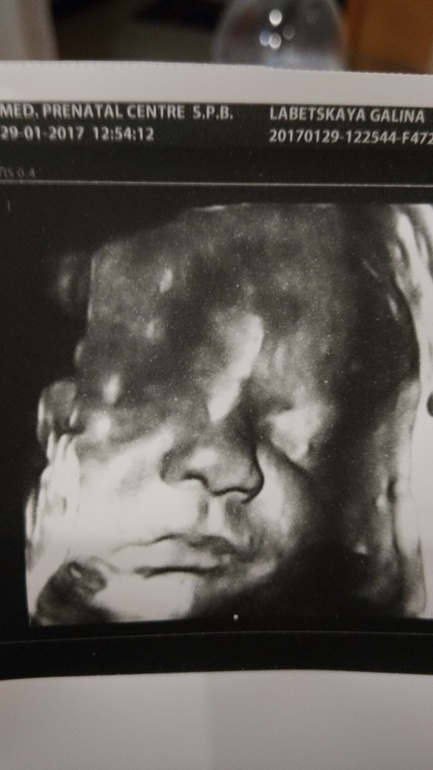

3й скрининг

Все у нас отлично! Вес на 31 неделю и 2 дня составляет 1969г

Мамонтенок. Немного неравномерный: голова на 34-35 недель. Живот на 32-33, а ноги на 31-32. Головастик растёт, умный будет!

Подтвердили сыночка, как и на 1м, и на 2м УЗИ.

И фото))